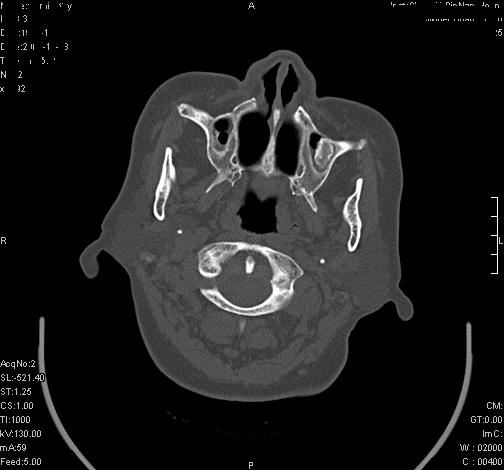

上次发的片子,不够细微。误导了大家,请大家再重新看一下,思路会更清晰。

双侧上颌窦上部黏膜明显增厚、窦腔缩小,偏后侧窦壁骨质毛糙、模糊,窦腔内见条块状钙化。结合双侧鼻甲黏膜明显增厚,以及临床症状,

考虑:双侧上颌窦霉菌性鼻窦炎

双侧上颌窦密度增高,粘膜增厚,内见条片状钙化,窦壁无增生与破坏征象,双侧鼻甲粘膜肥厚.

意见:双侧霉菌性上颌窦炎.

温习:真菌性鼻旁窦ct特征 1)非侵袭性病变者可涉及到鼻腔和鼻窦,多为单侧,上颌窦最多见.2)ct示窦腔内软组织增生影,可呈息肉状,+c可强化3)增生软组织影内可见散在斑片状或沙砾状钙化区,此为其典型特点,4)

非侵袭性病变可见窦壁骨质增生,破坏少见;侵袭性病变可见窦壁骨质破坏.

如此好的机器,为何不来点冠状面和失状面重建的图象呢,或许会提供更多的信息供大家参考。